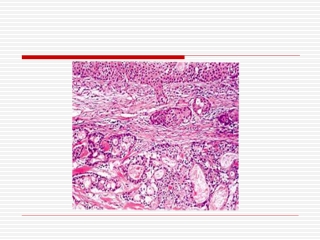

پاسخ :

تشخيص هاي افتراقي:

تشخيص نهايي

:

Low grade mucoepidermoid tumor